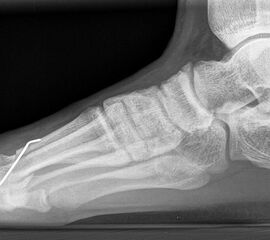

Röntgen

Standard ist die belastete Röntgenaufnahme des Fußes dorso-plantar und seitlich. Günstig ist eine Röhrenkippung von 10°-20°, um die Gelenke der Lisfranc-Linie einsehen zu können.

Ergänzend kann eine Schrägaufnahme hilfreich sein. Bei Metatarsalgien oder Pathologien der Sesambeine liefert die Sprinteraufnahme zusätzliche Informationen. Bei einer Pes planovalgus Fehlstellung wird ergänzend ein Saltzman view durchgeführt.

• Elevation/ Plantarisierung I. Strahl